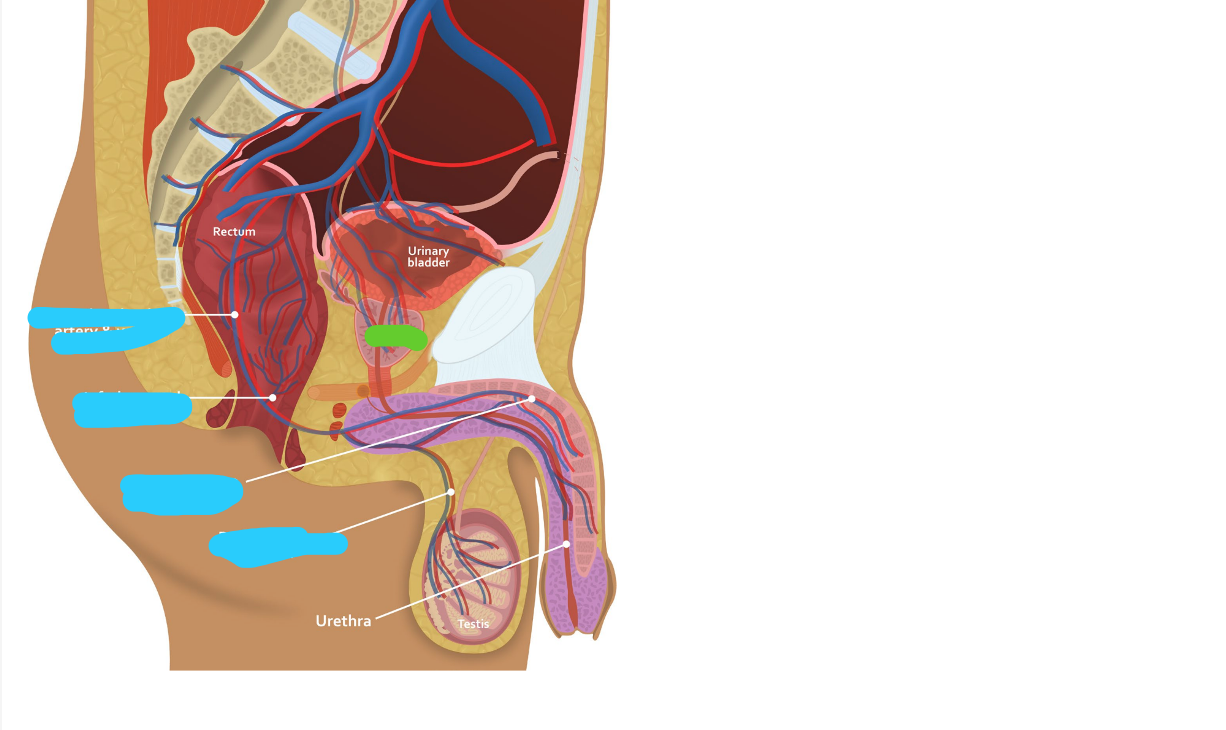

Name the vesicles (blue) and structure (green)